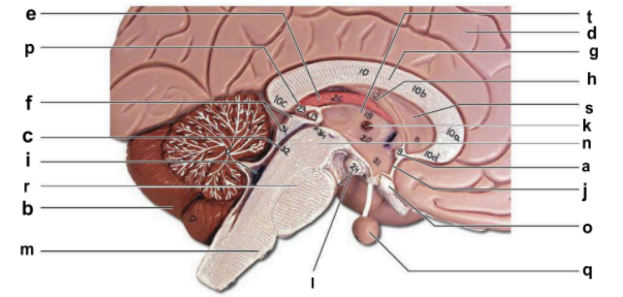

Identify the structure labeled “a” in the image.

anterior commissure

Identify the structure labeled “b” in the image.

cerebellum

Identify the structure labeled “c” in the image.

cerebral aqueduct

Identify the structure labeled “d” in the image.

cerebral hemisphere

Identify the structure labeled “e” in the image.

choroid plexus

Identify the structure labeled “f” in the image.

corpora quadrigemina

Identify the structure labeled “g” in the image.

corpos callosum

Identify the structure labeled “h” in the image.

fornix

Identify the structure labeled “i” in the image.

fourth ventricle

Identify the structure labeled “j” in the image.

hypothalamus

Identify the structure labeled “k” in the image.

interthalamic adhesion

Identify the structure labeled “l” in the image.

mammilary body

Identify the structure labeled “m” in the image.

medulla oblongata

Identify the structure labeled “n” in the image.

midbrain

Identify the structure labeled “o” in the image.

optic chiasma

Identify the structure labeled “p” in the image.

pineal gland

Identify the structure labeled “q” in the image.

pituitary gland

Identify the structure labeled “r” in the image.

pons

Identify the structure labeled “s” in the image.

septum pellucidum

Identify the structure labeled “t” in the image.

thalamus